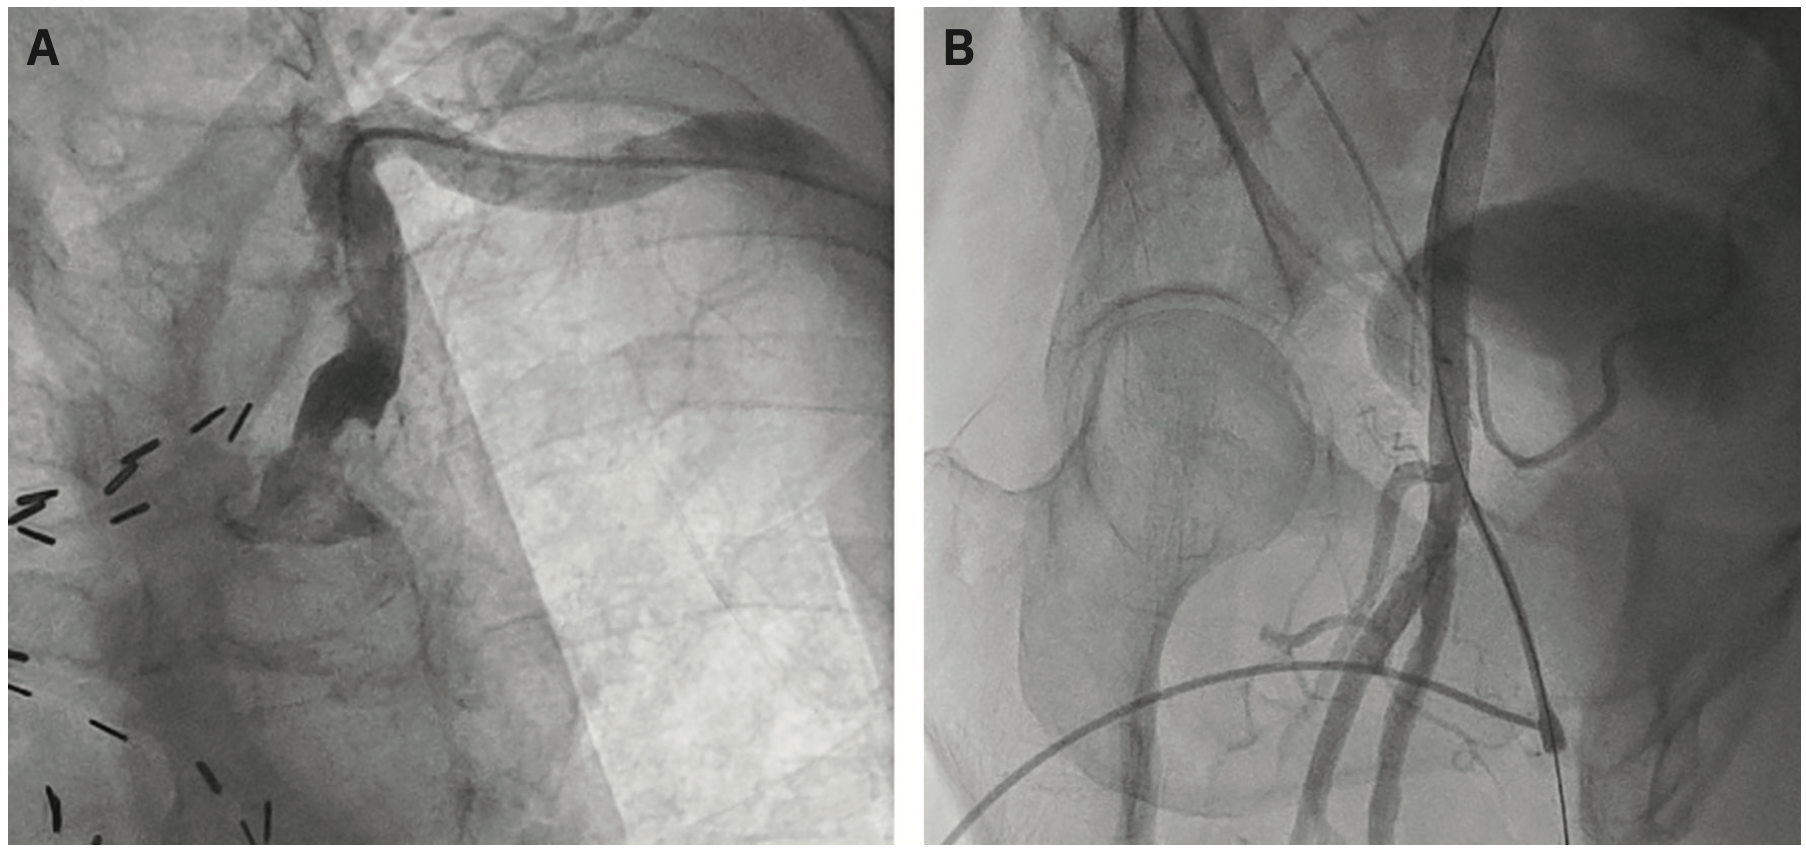

Our patient was elderly man who had angina 12 years after coronary artery bypass graft (CABG) surgery with a left internal mammary artery (LIMA) graft and 3 saphenous vein grafts (SVGs). His left ventricular ejection fraction (LVEF) had dropped to 35% compared to several years ago. As his body mass index was 35 kg/m2, and because we are of course a radial-first lab, we chose distal left radial artery access for his coronary angiography, using a 5 French (F) Judkins left (JL) 4 catheter to begin our study. Surprisingly, we encountered significant left subclavian tortuosity and a moderate atherosclerotic stenosis (Figure 1A), which prevented us from completing the angiography from the arm, despite several attempts using different catheters. After imaging the LIMA, we changed to right femoral access to complete the case. Femoral artery access was performed as described1,2 in a routine manner, but the patient’s protuberant abdomen and previous inguinal hernia surgery made access difficult. Using ultrasound guidance and micropuncture technique, we needed to exchange a regular .035-inch J wire for a stiff .035-inch Amplatz wire, and inserted incrementally larger dilators (4, 5, 6, and 7F) before we could insert the 6F sheath. Femoral angiography confirmed good sheath placement in the common femoral artery (Figure 1B). Coronary arteriography of the native vessels and SVGs was performed without problems. For hemostasis, we choose an Angio-Seal VCD anticipating the need for a stiff guidewire and some extra force to place the VCD sheath in the vessel. Both the scarring and angle of entry to the artery made this a challenge. After some struggle, the Angio-Seal vascular marker hole showed blood, indicating proper device position. The VCD was deployed with the usual 2 clicks (1 to expose the foot plug and the second click to deploy the foot in the vessel), followed by withdrawal of the device sheath, looking for the string to push the tamping tube down in order to pack the collagen wrap on the foot plate. But on pulling back the Angio-Seal, the entire device came out (Figure 2A) with no string, tamping tube, or foot plate. We immediately applied manual pressure to obtain hemostasis. At first, we thought the plug was retained, lost in the femoral artery. By reflex, I requested a call to vascular surgery while we tried to figure out where the plug ended up. Could the retention string and plug have been pulled into the artery and carried downstream? This seemed highly unlikely, but anything could have happened. We cut open the Angio-Seal delivery sheath and found the vascular plug intact, with the string still attached (Figure 2B). Our surmise was that although we had blood flow from the marker hole, the sheath was never in far enough to let the plug be deployed. We were very relieved that we had not lost the plug in the vessel.